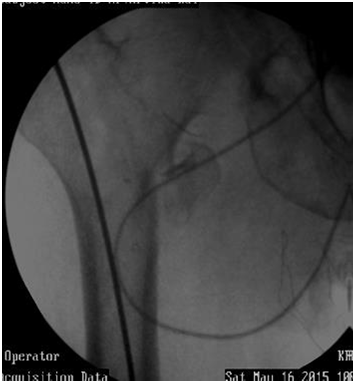

Remove Guide wire early, (Figure 20).

Figure 20 Guide wire may sink in canal while pushing nail down. Remove Guide wire early on.

Guide wire may sink in canal while pushing nail down. Remove Guide wire early on.